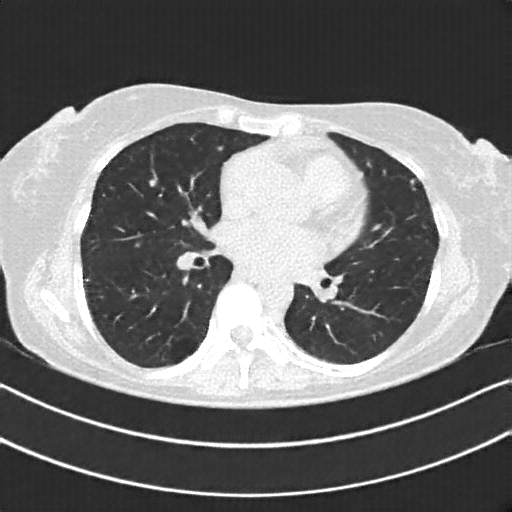

Original NATIVE CT scan (input)

Full window (WL 1023.5, WW 4095 β†’ Low βˆ’1024, High +3071)

Actual HU range: [-1024.0, 2097.0]

Lung window (WL -600, WW 1500 β†’ Low βˆ’1350, High +150)

Actual HU range: [-1024.0, 150.0]

Mediastinum window (WL 40, WW 400 β†’ Low βˆ’160, High +240)

Actual HU range: [-160.0, 240.0]